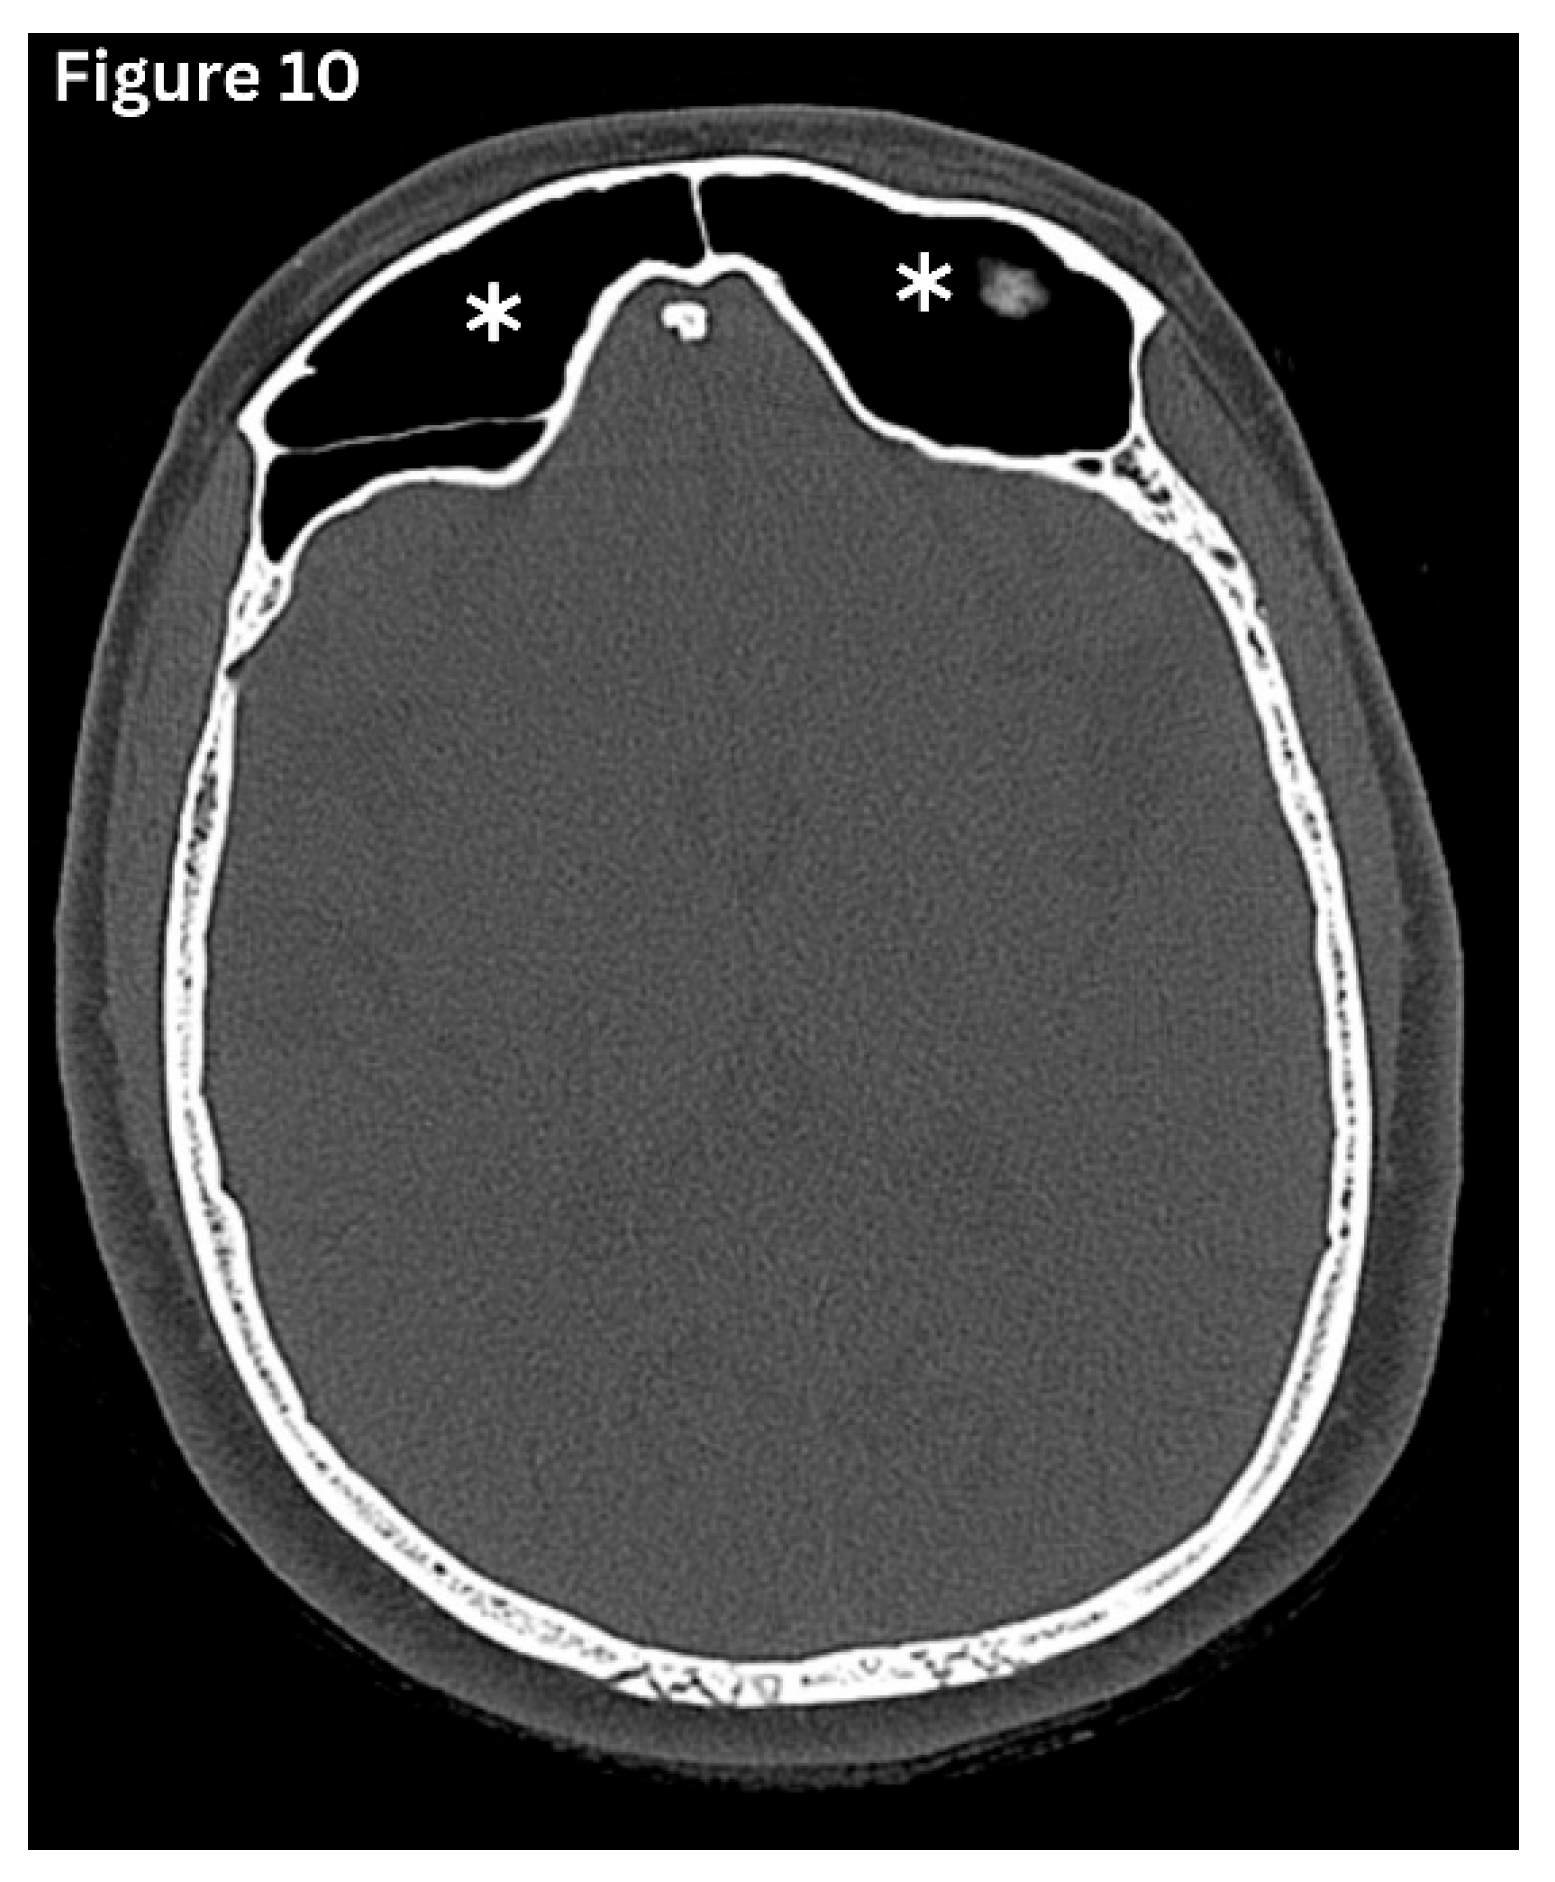

Pneumosinus dilatans (PSD)is characterised by abnormal expansion of a paranasal sinus beyond its normal boundaries, while maintaining normal mucosal lining and preserving bony walls. (Figure 9 and Figure 10) It is a developmental variant and is most often seen in the frontal, sphenoid, and maxillary sinuses. PSD most often affects a single sinus rather than multiple cavities, with isolated involvement reported in nearly 80% of cases [14]. It is frequently detected incidentally on imaging. However, some may present with frontal bossing and a spectrum of visual disturbances, including proptosis, diplopia and headache. This predisposes to recurrent episodes of sinusitis due to impairment of normal sinus drainage [14].

Figure 10. Axial CT image shows excessive pneumatisation of both frontal sinuses.